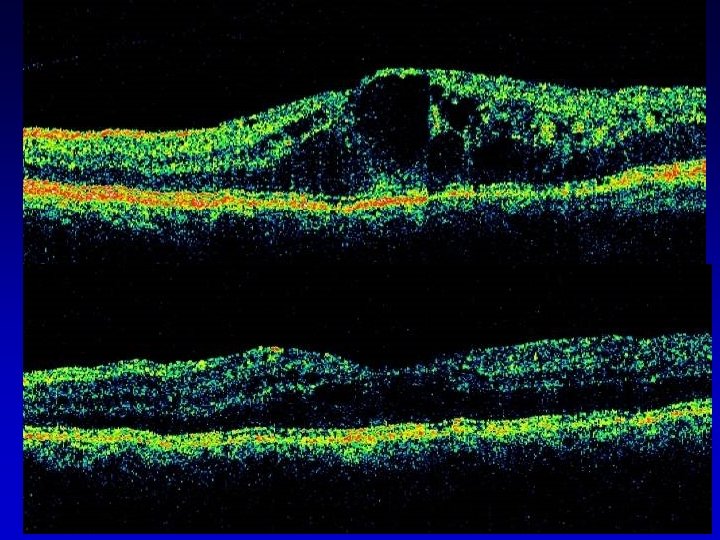

ESAMI DIAGNOSTICI OFTALMOSCOPIA E BIOMICROSCOPIA F A G (EV. ICG) ECOGRAFIA OCT ESAMI ELETTROFUNZIONALI

TRATTAMENTO PARACHIRURGICO FOCALE: microaneurismi con diffusione tra 400 -3000 micron dalla fovea; lesioni tra 300 -500 micron dalla fovea se visus <= 5/10 A GRIGLIA: edema maculare PANFOTOCOAGULAZIONE: aree ischemiche > 10Ø papillari CRIOPESSIA TRANSCONGIUNTIVALE DELLA RETINA PERIFERICA: opacità del cristallino, rubeosis iridis, glaucoma neovascolare con residuo visivo